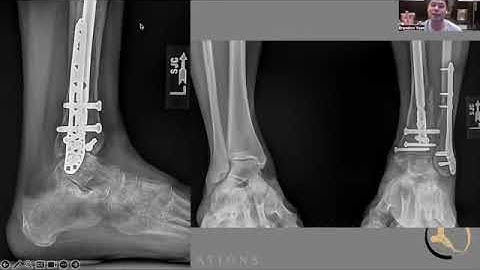

PROXIMAL TIBIAL FRACTURES ‘DECISION MAKING IN MANAGEMENT’